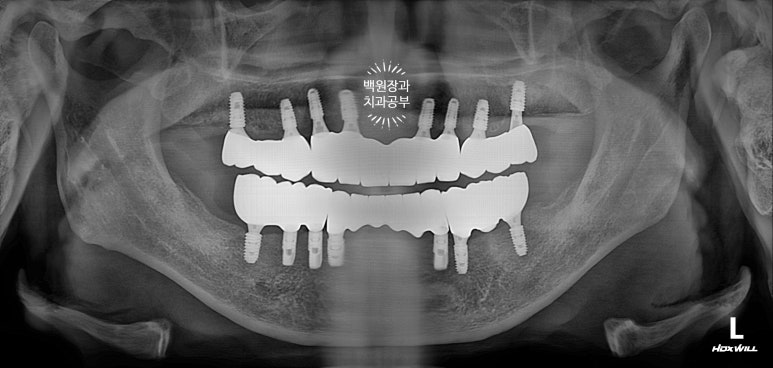

완성 후 치과용 파노라마 사진을 찍었습니다.

저희 치과에서 사용하는 오스템임플란트 네비게이션 시스템을 통해 임플란트 위치를 잘 계획하였고, 그 덕분에 각 치아의 가운데에 잘 맞춰져 임플란트가 위치된 것을 보실 수 있어요.

아래턱에서는 임플란트 주위염이 심했던 왼쪽 아래 임플란트 하나를 제외한 3개를 사용하기로 하여서, 4개만 추가로 심기로 하였고 위턱은 총 8개를 심어드리기로 계획하였습니다.

전체 틀니와 임플란트 틀니에서 전체 임플란트로 바꾸기 위해 총 12개의 임플란트를 추가로 심게 되었네요.